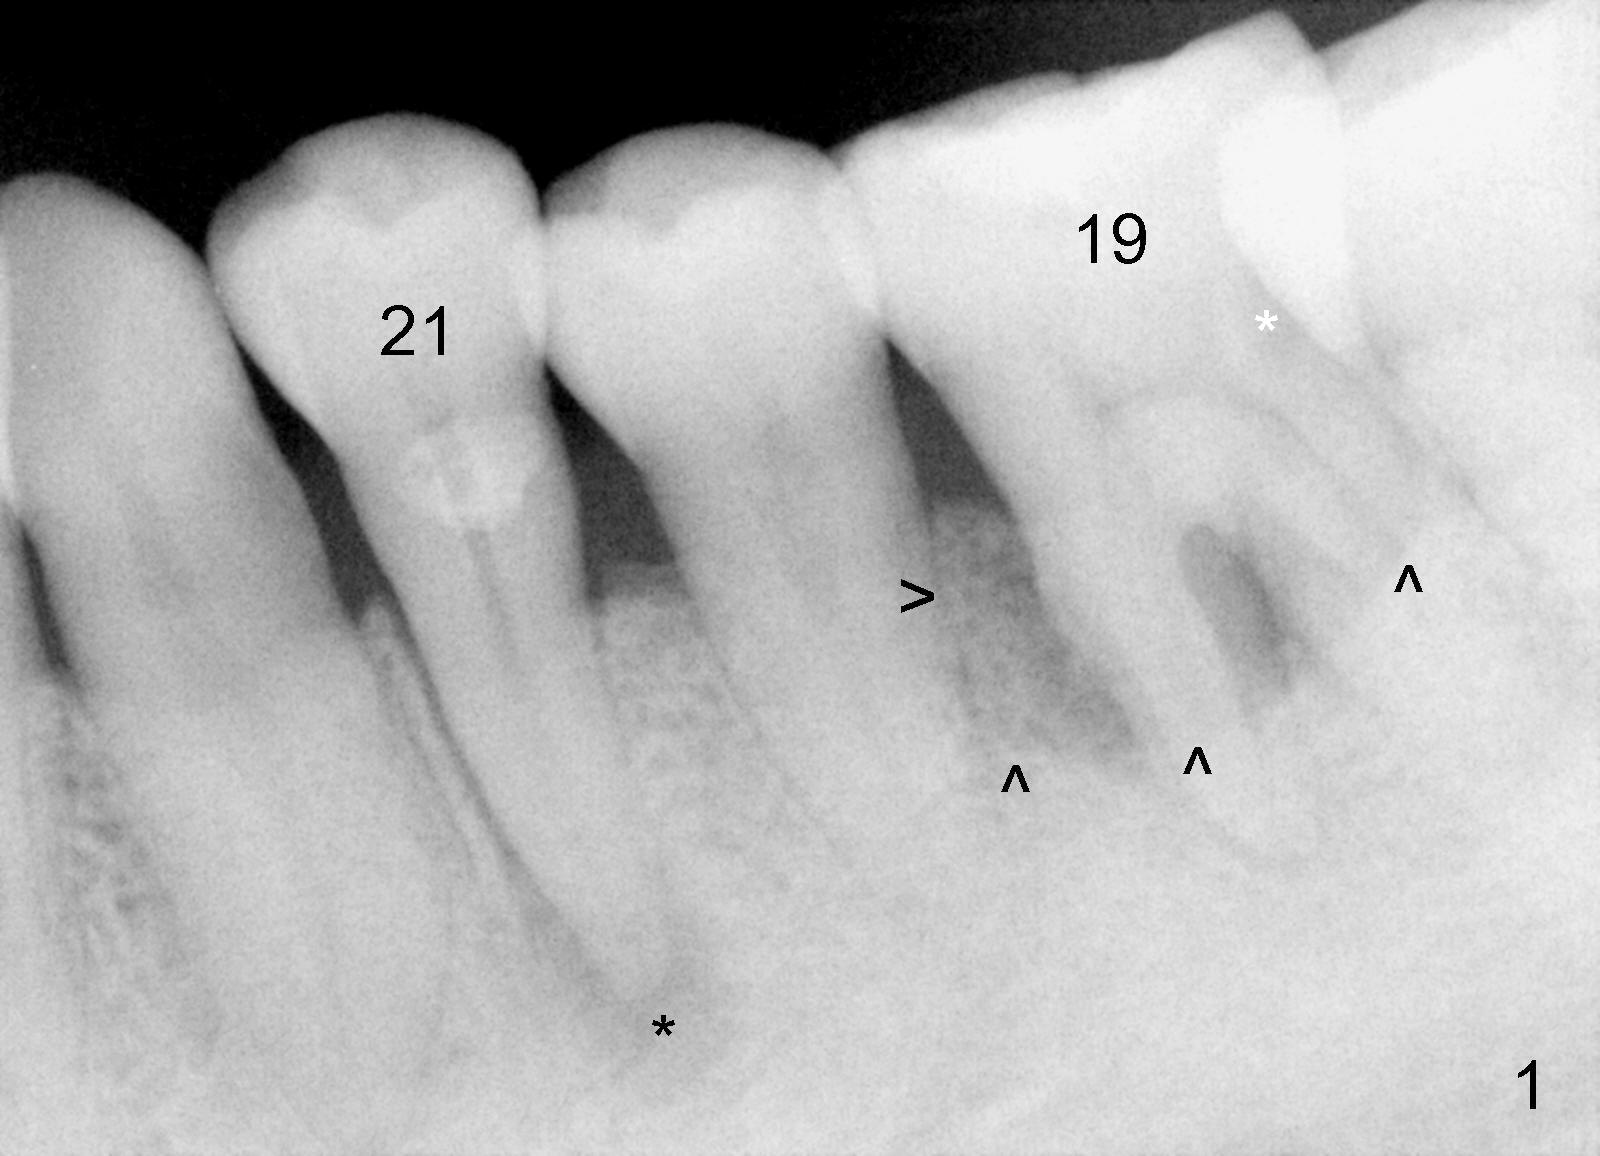

A 48-year-old lady has poor dentition. Four years and a half ago when the tooth #21 needed root canal therapy (RCT), the tooth #19 showed bone loss (Fig.1 arrowheads) and hidden caries (white *). The carious lesion caused severe toothache 2 years later (Fig.2 *), while the perio lesion remain severe. The tooth #19 received RCT; the patient remained asymptomatic until recently. Since the patient is satisfied with immediate implant with the tooth #2 (mainly perio lesion), she is not hesitant in accepting the same mode of treatment for #19.